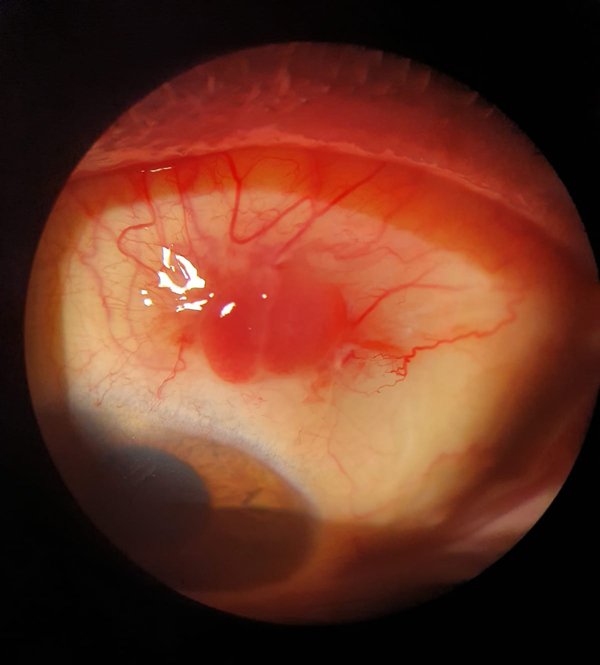

El paciente acudió a control postoperatorio con agudeza visual mejor corregida (AVMC) en OI 20/25; en la BMC, OI con injerto vital en posición y correcta reepitelización en sitio de obtención de autoinjerto. Se le indicó tratamiento con moxifloxacina 0,5% y dexametasona 0,1% cada 4 horas más lagrimas artificiales. Dos semanas posteriores a la extracción de puntos se visualizó injerto en posición, conjuntiva súpero-temporal con mala cicatrización y lesión granulomatosa de 4 x 5 mm en sitio de obtención del injerto (fig. 1). Se indicó tratamiento con prednisolona oftálmica 1%, 4 veces día y lágrimas artificiales.

Figura 1. Lesión granulomatosa en el área de cicatrización.